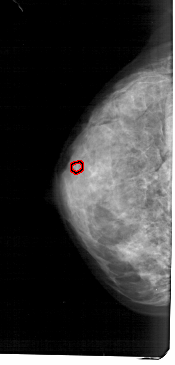

A_1684_1.LEFT_CC

LEFT_CC LINES 5101 PIXELS_PER_LINE 2446 BITS_PER_PIXEL 12 RESOLUTION 43.5 OVERLAY

FILE: A_1684_1.LEFT_CC.OVERLAY

TOTAL_ABNORMALITIES 1

ABNORMALITY 1

LESION_TYPE CALCIFICATION TYPE PLEOMORPHIC DISTRIBUTION CLUSTERED

ASSESSMENT 4

SUBTLETY 2

PATHOLOGY BENIGN

TOTAL_OUTLINES 1